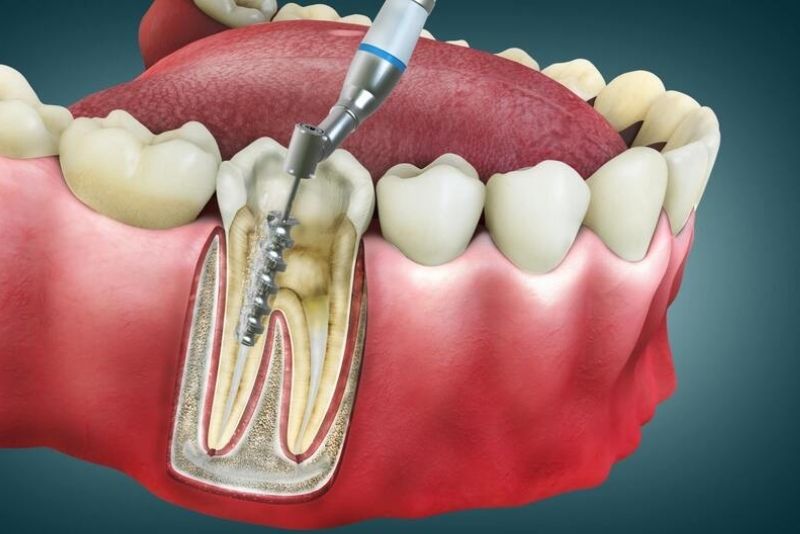

1. Tại sao cần bọc răng sứ sau khi lấy tủy?

Cần bọc răng sứ sau khi lấy tủy để bảo vệ răng khỏi bị gãy vỡ, sứt mẻ vì răng mất tủy sẽ yếu đi, giòn và không được nuôi dưỡng. Đồng thời khôi phục chức năng ăn nhai, ngăn ngừa vi khuẩn xâm nhập, tránh hôi miệng, và cải thiện màu sắc răng bị sẫm.

- Bảo vệ cấu trúc răng: Sau khi lấy tủy, răng mất nguồn nuôi dưỡng nên giòn, khô và dễ nứt gãy, đặc biệt khi chịu lực ăn nhai. Mão sứ giúp bao bọc và gia cố răng hiệu quả.

- Ngăn ngừa vi khuẩn xâm nhập: Lớp sứ đóng vai trò như hàng rào bảo vệ, ngăn thức ăn và vi khuẩn xâm nhập vào khoang tủy rỗng, giảm nguy cơ tái nhiễm, sâu răng và hôi miệng.